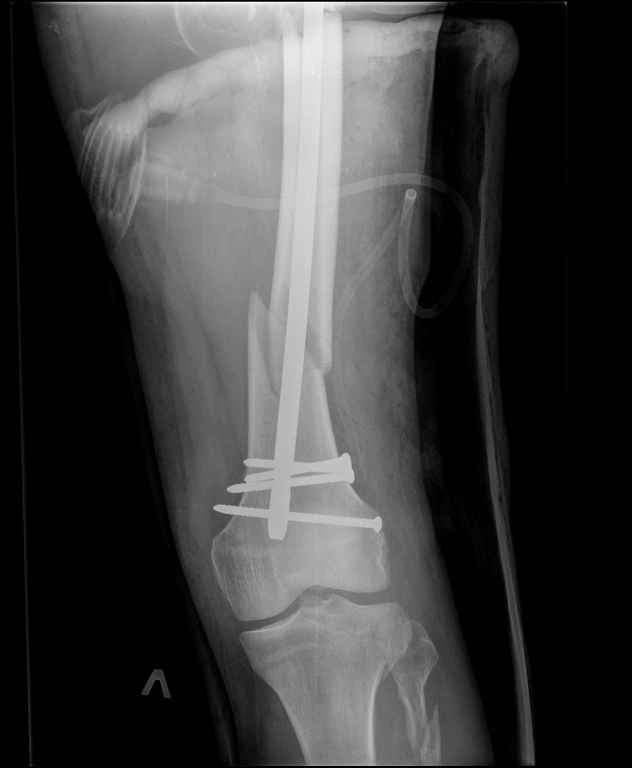

Неделю назад поступил пациент после ДТП. В тяжелом

состоянии. Ds: ТСТ. ЗЧМТ. СГМ. ЗТГК. О/фрагментарный перелом левого бедра. З/оскольчатый

перелом с\3 левого плеча. Перелом левого локтевого отростка. З/перелом наружного мыщелка

б/берцовой кости в/3 м/берцовой кости левой голени. при поступлении, ПХО раны левого бедра(

рана 1х1см по наружной поверхности бедра в с/3) налажено скелетное вытяжение , и гипсовая

лонгета на левую в/конечность.Находился в реанимации.

17.02.11был прооперирован: БИОС левого плеча, о/синтез левого

локтевого отростка по Веберу, БИОС левого бедра( длинная

версия Fi-Can Sanatmetal диаметр 10мм), мыщелок голени трогать не стали.при остеосинтезе

бедра возникли трудности при закрытй репозиции перелома в н/3, в связи с чем решили открыться

внизу , отрепонировали без особого труда и выполнили блокирование во фронтальной плоскости

3-мя винтами + 1 винт спереди гвоздя( промазал). Убрал костодержатель, все нормально,

контроль ЭОПом стояние отломков нормальное, зашились. На контрольной R-мме на утро

выявлено вторичное смещение дистального отломка. Левая нога по сравнению со здоровой

удлиннена до 2,5см( это за счет вальгусной установки гвоздя в проксимальном отделе, боялся

свалиться на варус).

Теперь думаем как поправить положение отломков в н/3, и зафиксировать

так чтобы не съехало. Наше предложение расшиться в н/3 бедра, разблокироваться, перелом

отрепонировать вновь и установить 1или 2отклоняющих винта в сагитальной плоскости, затем

заблокироваться во фронтальной плоскости снова. Помогите советом, как выйти достойно из

сложившейся ситуации. Заранее спасибо.